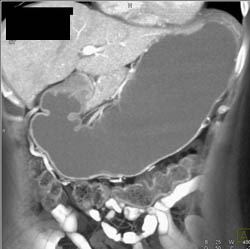

Diagnosis

Gastritis